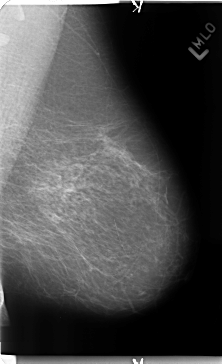

Digital Database for Screening Mammography

Volume: benign_04 Case: B-3155-1

B_3155_1.LEFT_MLO

LEFT_MLO LINES 4720 PIXELS_PER_LINE 2880 BITS_PER_PIXEL 12 RESOLUTION 50 NON_OVERLAY